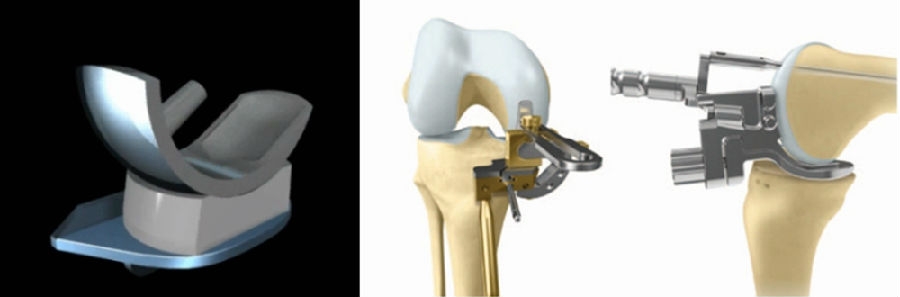

活动平台单髁(OUKA)优秀的设计,辅以友好的工具MP,目前已经取得了非常好的一些临床疗效。

未来如何实现单髁更精准、更微创,可能需要不同维度的解决方案。首先就是机器人,目前机器人比较火,因为其精准度比较高,但是它需要购置专用设备,价格昂贵,而且不利于在基层开展,特别是在目前的经济环境下;同时机器人设备需要占据空间,术中需要专门的工程师配合,术中需要注册,手术时间相对延长等特点。

对于单髁来说,考虑的另外一个解决方案就是3D打印导板结合AI。其具有精准度较高,不需要购置专用设备,价格亲民,利于在基层开展,不需要额外的设备空间,不需要术中专门的工程师配合等特点。但是,同时术中需要清除软骨和贴附导板可能会导致手术操作时间相对延长。